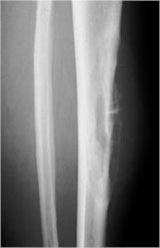

- Diaphyseal lesion on external surface of bone; medullary canal uninvolved

- Radiolucent mass extending into surrounding soft tissues

- Saucerized cortex with chondroblastic soft tissue mass that is usually primarily radiolucent on plain X-rays

- Periosteal reaction usually most evident feature on surface of bone (Hair on End or Sunburst appearance with spiculated pattern of calcification oriented perpendicular to the bone)

- Rare intramedullary invasion